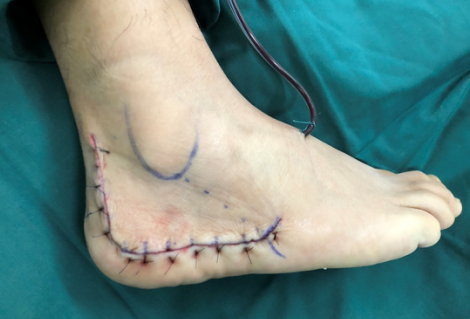

两位患者的手术效果都非常好,很快就要出院了。他们对俞教授和sararz足踝团队充满了感激之情。